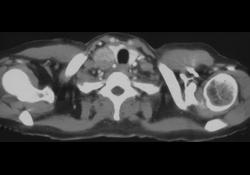

Invasive Pulmonary Aspergillosis (IPA)